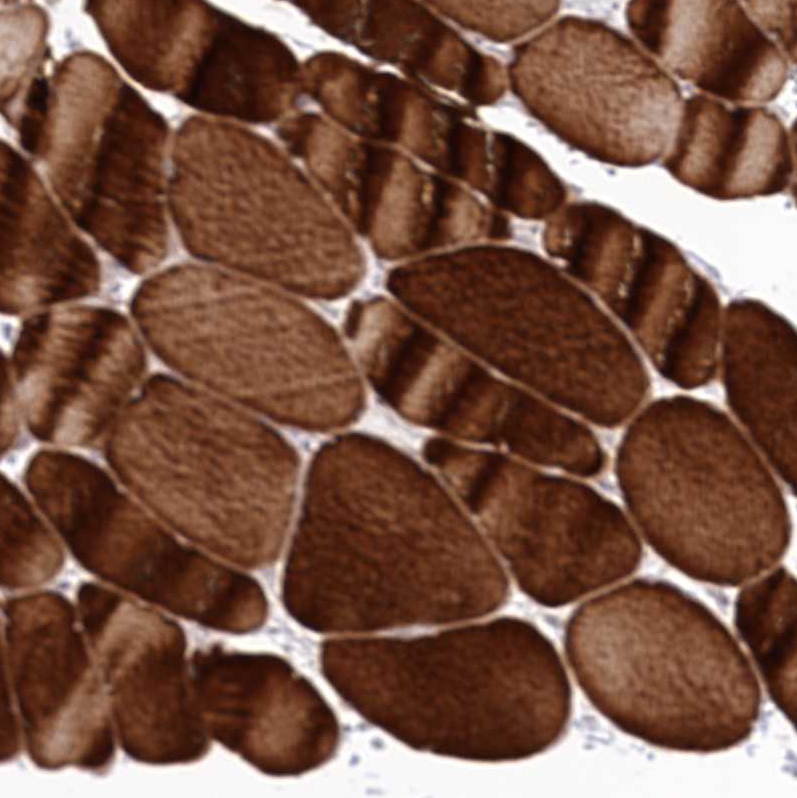

Immunohistochemical staining of human thyroid gland shows strong cytoplasmic positivity in glandular cells.